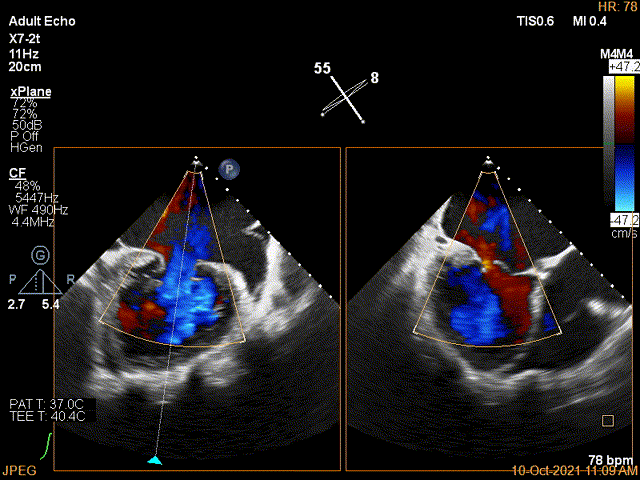

3D-color证实残余分流主要位于内侧2区

第一个夹子放置后二尖瓣口平均跨瓣压差:4mmHg

Color第二个夹子内侧残余小束分流,宽2.3mm